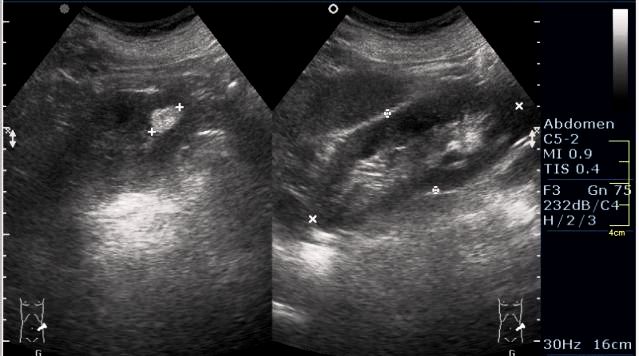

Женщина 50 лет. Жалоб нет. Обследование перед поездкой в санаторий по поводу дисфункции гепатобилиарной системы.

Случайная находка в нижней трети левой почки (не в полюсе, а по задне-медиальной поверхности).

PS. Кстати, а что это у нее рядом с правым надпочечником?

ПО УЗ-семиотике образование соответствует ангиомиолипоме (AML). По правилам в таких случаях необходимо выполнить КТ, доказать преимущественно жировой состав опухоли, затем проводить УЗ-наблюдение.

Согласен. Именно с таким диагнозом (ангиомиолипома) отправил на КТ. Особенностью случая ИМХО является заметный "выход" образования за контур почки (на 2/3 объема).

PS. А надпочечник в срез не попал. Что-то, возможно, прилежит к области проекции надпочечника и к верхнему полюсу почки.

При ультрасонографии ангиомиолипома выглядит как округлое образование без капсулы с однородной внутренней эхоструктурой и четкими контурами; эхогенность ее чаще всего равна или чуть выше эхогенности перинефральной клетчатки [7]. Значительно реже эхогенность ангиомиолипом может быть равна эхогенности почечной паренхимы; такие опухоли состоят почти полностью из гладкомышечной ткани [8]. Иногда позади ангиомиолипомы может определяться слабая акустическая тень.